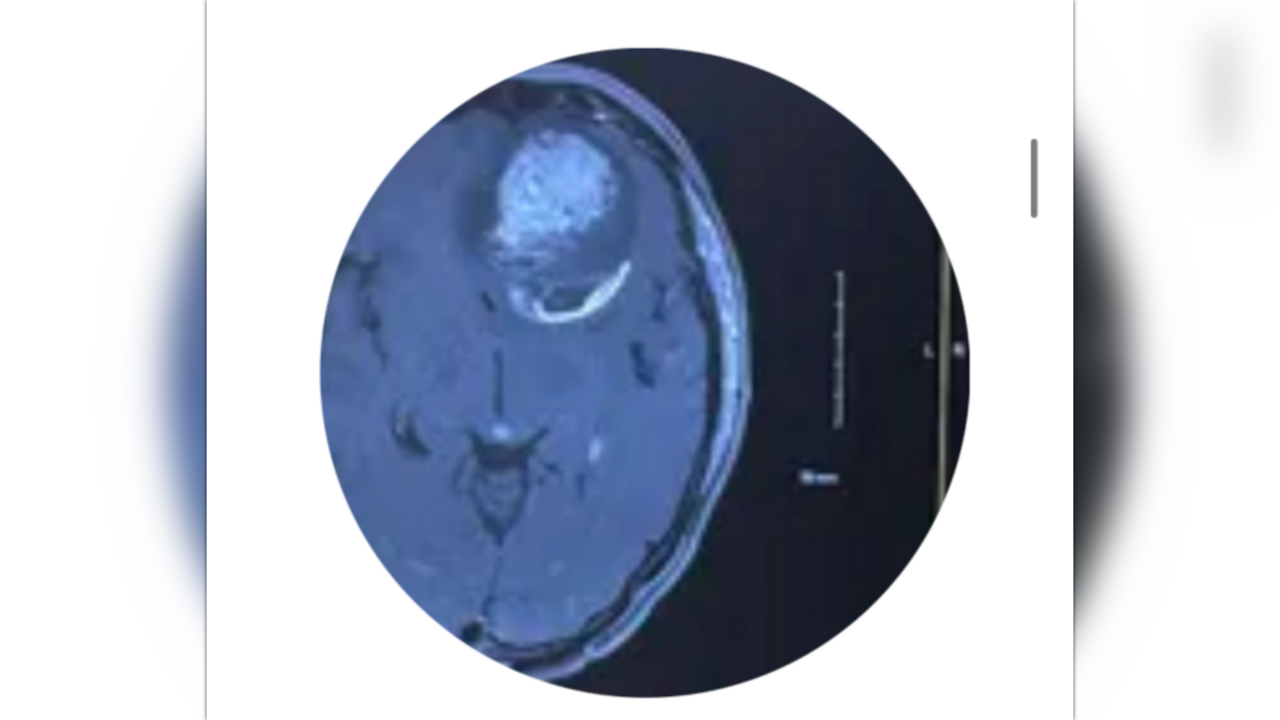

At the end of  June 2024, Nathan began suffering from  uncontrollable headaches  while at work. He went to  Divine Savior Hospital  in Portage, WI several times, only to be sent home each visit. Finally, a doctor ran a  CT scan  and found a  mass on his brain  — but even then, they sent him home again.

Not long after, Nathan became  unresponsive  at home. His wife immediately knew something was wrong and rushed him to another hospital, where doctors  performed emergency brain surgery  the next day to remove the tumor. By the grace of God, he survived, and our family was beyond thankful to still have him with us.

Two weeks later, we received devastating news: Nathan was diagnosed with  glioblastoma, an aggressive and  incurable brain cancer. The odds of survival are low, but if you know Nathan, you know he’s a fighter. He’s kept his  faith in God  and prays every day for strength and healing.

Recently, doctors found a  second tumor  on his  brain stem, and it has started to  affect his mobility  — his arms often go numb, and he can no longer run. Worst of all, doctors have now given him  only two months to live.